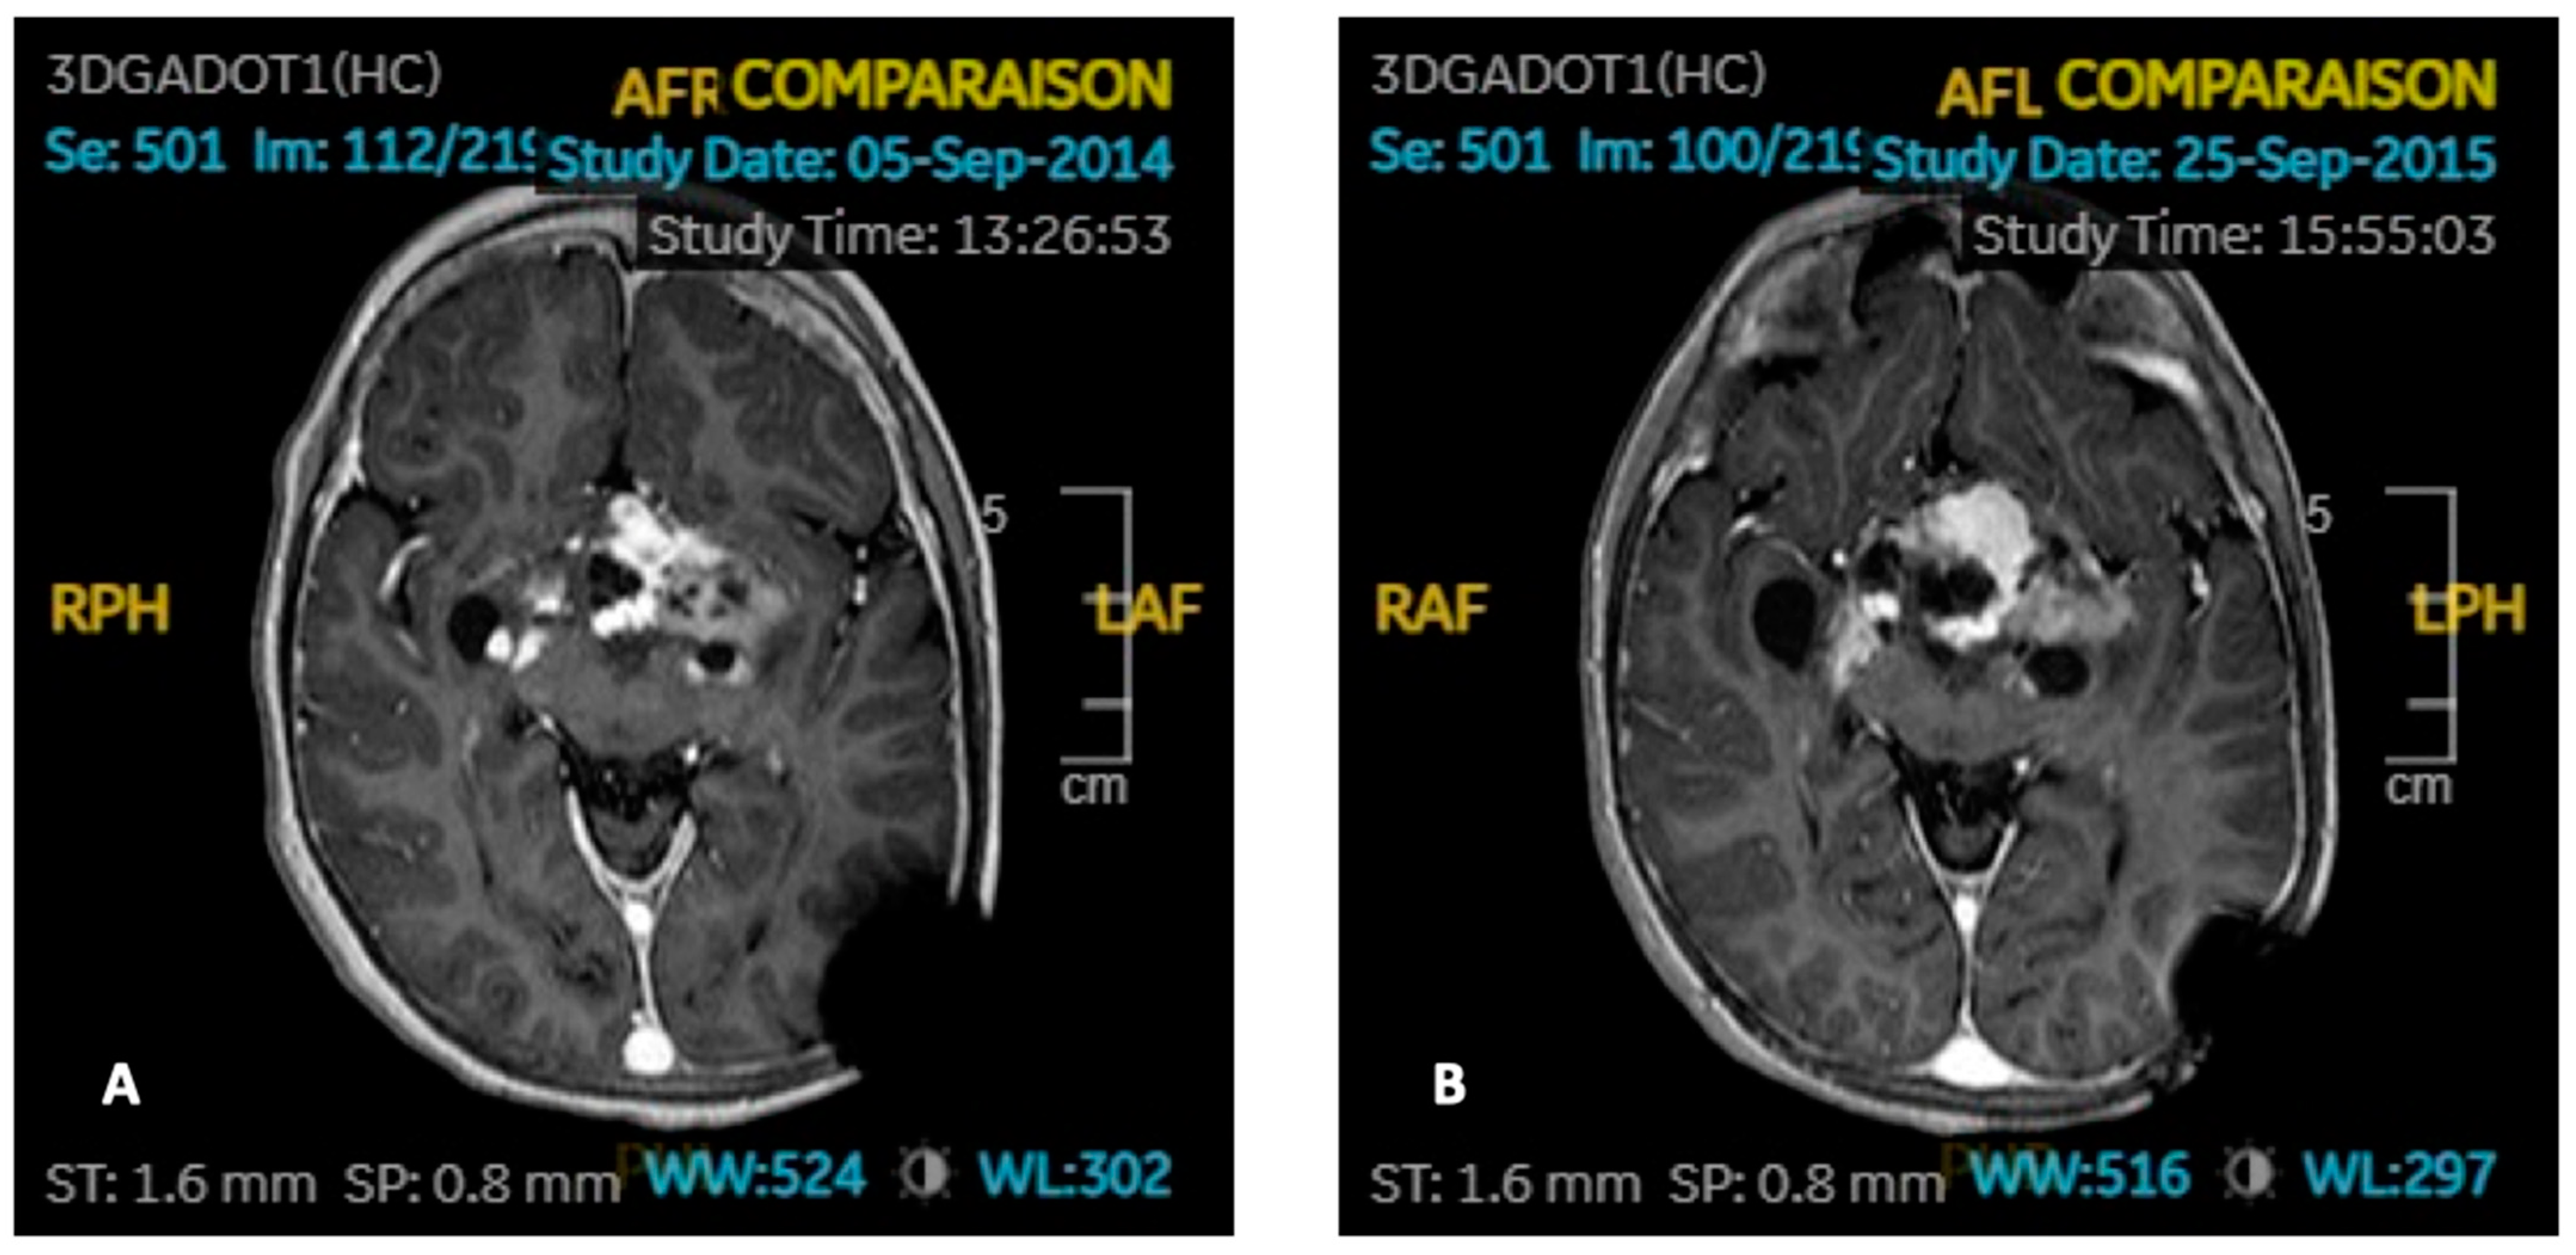

3.4. Particularities in GH Substituted Patients